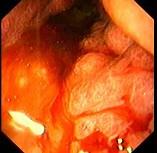

问题 男性患者,45岁,平素身体健康,近2个月出现上腹饱胀不适,偶有隐痛,伴纳差,近2天有黑粪,胃镜如图。关于本病,下列说法正确的有 ( )

选项 A、处于进展期 B、应马上手术治疗 C、可诊断为胃间质瘤 D、处于早期 E、可诊断为胃癌

答案 ABE